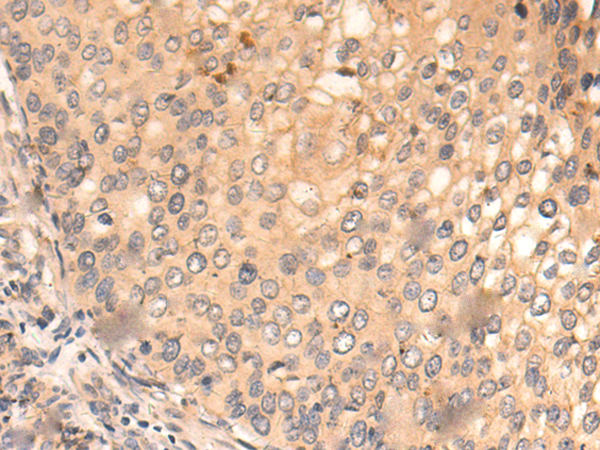

分类: 科研抗体货号: P03331别名: CAF1; CAF-1; Caf1a; hCAF-1应用: IHC反应种属: Human, Mouse